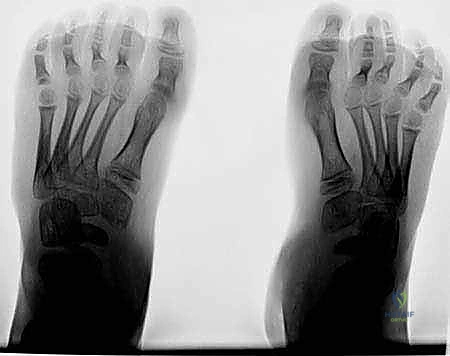

الشكل 1 • تشوهات القدم الجوفاء، منظر جانبي. لاحظ زيادة الانثناء الأخمصي لمقدمة ومنتصف القدم بالنسبة لمؤخرة القدم، وهو ما يسبب ضغطًا هائلاً على مشط القدم.

الشكل 2 • تشوهات القدم الجوفاء، منظر أمامي. يوضح مكونات انقلاب الكعب للداخل وتقوس مقدمة القدم، مما يؤدي إلى عدم استقرار الكاحل.